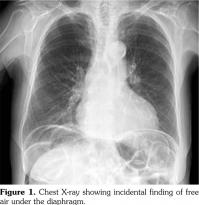

A 62-year-old female patient, diagnosed with mixed connective tissue disease (MCTD) five years priorly, presented with incidental findings of pneumoperitoneum on an outpatient chest X-ray (Figure 1). At initial diagnosis, she had inflammatory polyarthritis as evidenced by synovitis at the metacarpophalangeals and proximal interphalangeals bilaterally, Raynaud’s phenomenon, and swollen fingers (sausage appearance) with associated sclerodactyly. Serology showed positive anti-nuclear antibody (1:1200) and anti-ribonucleoprotein. All other autoantibodies were negative. She had initially been managed with oral steroids but was never on any immunosuppressant due to mild disease and patient preference. She had a history of vague abdominal discomfort, dysphagia and diarrhea since diagnosis, and did not report worsening of her baseline symptoms. On presentation to hospital, she was hemodynamically stable and her physical examination revealed a non-tender abdomen with no evidence of peritonitis. The patient had multiple comorbidities, which were severe chronic obstructive pulmonary disease, remote viral cardiomyopathy, small intestinal bacterial overgrowth (SIBO) and gastroesophageal reflux disease. She was not on corticosteroids, antibiotics or any immunosuppressant.